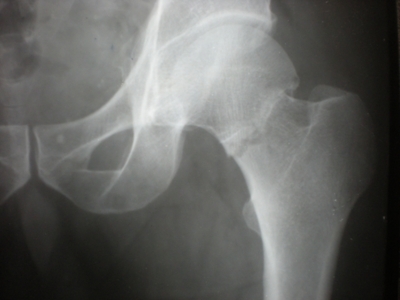

Quel diagnostic? Quelle doit être la déformation clinique du membre inf? Doit-on la réduire?

Fracture de l’ES du fémur gauche Garden 1

coxa valga

engrènement du foyer de fracture= stable = pas de réduction